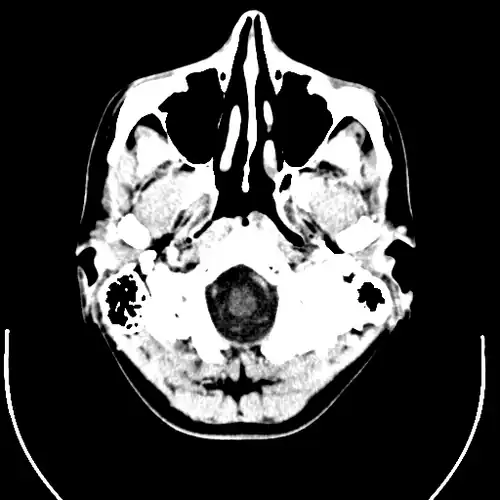

De neusholte is een met lucht gevulde ruimte achter en net boven de neus, in het midden van het gezicht.